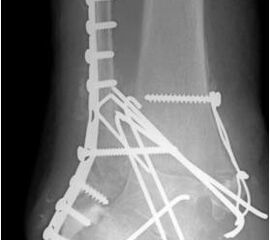

• Primäre oder posttraumatische Arthrose des OSG und USG (Abbildung 1, Abbildung 2).

• Revision einer gescheiterten Fusion des OSG/ USG (Abbildung 3, Abbildung 4).

• Pseudarthrosen (Abbildung 5, Abbildung 6).

• Ausgeheilte (!) Osteomyelitiden (Abbildung 7, Abbildung 8, Abbildung 9, Abbildung 10).

• Spezielle Indikationen (Abbildung 11, Abbildung 12).